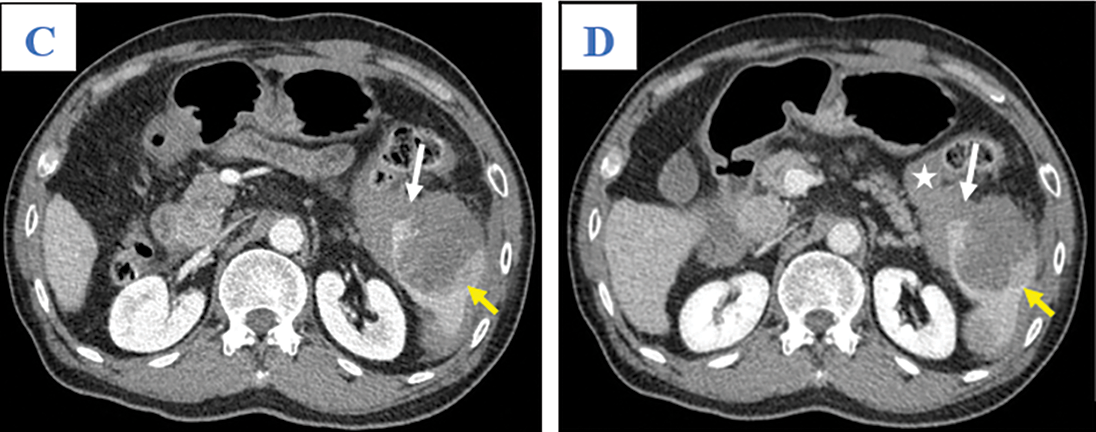

A 65-year-old man was admitted to our hospital complaining of fatigue and mild left-side abdominal pain without any history of recent trauma. He had a history of chronic hepatitis B infection for the past 6 years. Physical examination revealed a palpable mass below the left costal margin, which was defined as an enlarged spleen on abdominal ultrasound. Additionally, multiple nodules and masses were detected in the spleen and liver on ultrasonography. The patient was transferred to the oncology department with suspicion of metastatic disease with an unknown primary. Two days after admission, the patient developed severe acute abdominal pain, hypotension (80/50 mmHg), and tachycardia (105 beats per minute). Laboratory tests revealed a low hemoglobin (85 mg/dL), elevated alpha-fetoprotein (AFP; 8757 ng/mL), and elevated protein induced by vitamin K antagonist II (PIVKA-II; 23043.11 AU/mL). Bedside ultrasonography detected free intraperitoneal fluid with mixed internal echogenicity, suggesting hemoperitoneum. Therefore, urgent CECT was performed, which revealed a large quantity of hyperdense, free fluid in the pelvis and surrounding the inferior splenic pole, most consistent with hemoperitoneum (Fig. 1A). Multiple splenic masses were observed, with the largest in the inferior pole measuring 6 x 6 cm. The masses were hypodense on pre-contrast images (Fig. 1A) and demonstrated mild heterogeneous enhancement in the arterial phase (Fig. 1B), without gross change on portal venous (Fig. 1C) or delayed phase images (Fig. 1D). Discontinuity of the splenic capsule consistent with tumor laceration, was observed on post-contrast images without signs of active bleeding (Figs. 1C and 1D). In addition, multiple hepatic masses were observed, which were hypodense on pre-contrast images, and demonstrated marked peripheral hyperenhancement in the arterial phase, and non-peripheral washout in the portal venous and delayed phase images (Figs. 2A–2C). Right anterior portal vein thrombosis (Fig. 2D) was also identified. Multiple enlarged lymph nodes were observed in the hepatic hilum and paraaortic space, in addition to osteolytic lesions in the fourth and eighth thoracic vertebral bodies. The patient was diagnosed with hemoperitoneum due to presumed ruptured splenic metastasis, and an emergency splenectomy was performed. A liter of blood in the abdomen and a lacerated splenic mass were found on surgical exploration. Histopathology revealed a solid tumor with a well-defined margin between the tumor and the splenic parenchyma (Fig. 3A). The tumor cells were arranged in a trabecular pattern, with prominent nucleoli and hyperchromatism (Fig. 3B). Immunohistochemically, the neoplastic cells revealed solid and diffuse positivity for the hepatic marker hepatocyte paraffin 1 (HEPAR-1), indicating an HCC origin (Fig. 3C). The patient was diagnosed with Grade 2 HCC, with splenic and bone metastases, and metastatic abdominal lymphadenopathy. The patient was treated with targeted therapy. Finally, this patient was lost to follow-up.

Figure 2: Axial abdominal CT in the pre-contrast (A), Arterial (B), Venous phases (C), and Delayed phase (D). The nodular liver contour in this patient with chronic hepatitis B in segment VII appeared hypodense in the pre-contrast image (A; yellow arrow), peripherally hyper-enhancing in the arterial phase (B; yellow arrow), and without washout in the venous phase (C; yellow arrow). Other hepatic lesions are not shown in these images. Note thrombus in the anterior segmental branch of the right branch of the portal vein (D; white arrow)